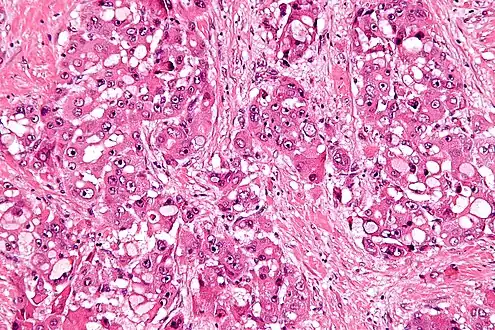

| Micrograph of fibrolamellar hepatocarcinoma showing the characteristic laminated fibrosis between the tumor cells with a low NC ratio. H&E stain. | |

The histopathology of FHCC is characterized by laminated fibrous layers, interspersed between the tumor cells. Cytologically, the tumor cells have a low nuclear to cytoplasmic ratio with abundant eosinophilic cytoplasm. Tumors are non-encapsulated, but well circumscribed, when compared to conventional HCC (which typically has an invasive border).